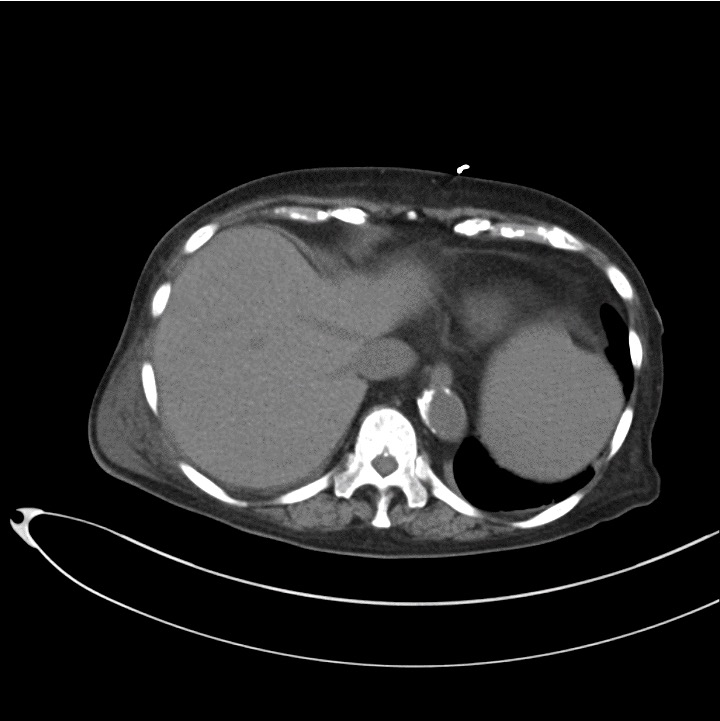

発熱,下腹部痛,意識障害を呈する70歳代女性

病歴:

2日前から発熱と下腹部痛を認めた.今朝からは意識がもうろうとしていることに家人が気づき,患者とともに受診.

身体所見:

体温38.9℃,下腹部正中~右下腹部あたりに圧痛,自発痛あり.

既往歴:

糖尿病,高血圧,慢性腎不全(人工透析中).

血液検査:

WBC,CRP上昇.

Q1:腹部単純CT(図1)の画像所見は?

Q2:診断は?

図1 腹部単純CT横断像